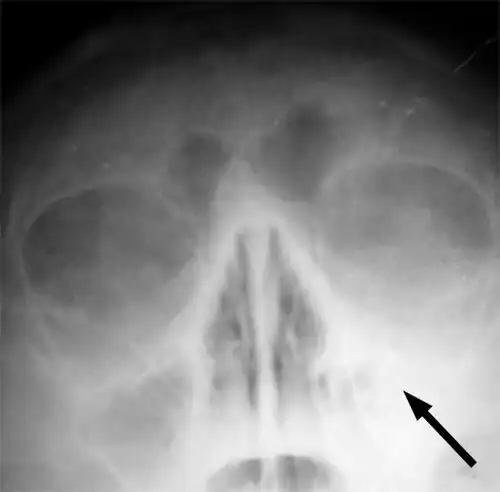

Imaging by either X-ray, CT, or MRI is generally not recommended unless complications develop.[66] Pain caused by sinusitis is sometimes confused for pain caused by pulpitis (toothache) of the maxillary teeth, and vice versa. Classically, the increased pain when tilting the head forwards separates sinusitis from pulpitis.[68]

For cases of maxillary sinusitis, limited field CBCT imaging, as compared to periapical radiographs, improves the ability to detect the teeth as the sources for sinusitis. A coronal CT picture may also be useful.[60]